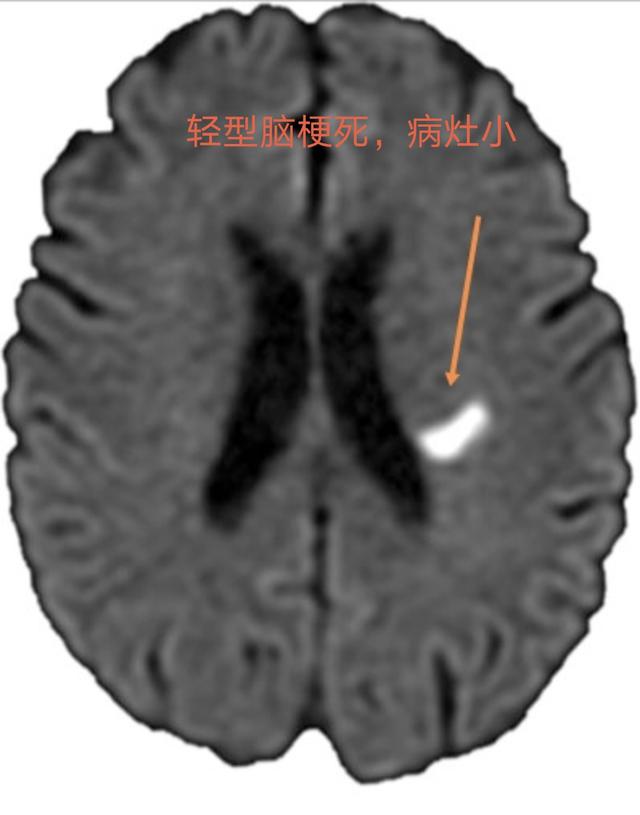

軽度の脳梗塞(「ミニ脳卒中」)。小血管の閉塞による突然の局所的な軽度の神経機能障害である。(期間≥24時間)最も一般的な症状は以下の通りである。軽い手足の脱力感やしびれ、不明瞭な発語、口の曲がり、平衡感覚の障害、意識障害は伴わない。ほとんどの梗塞は小さいか、非運動機能領域にあり、80%はラクナ梗塞であり、ほとんどは重大な障害を残さない。しかし、脳組織に永久的な損傷を与える。

軽度の脳梗塞の場合、梗塞の程度は小さく、症状も軽いのですが、脳の組織がダメージを受けているため、対処が遅れると一定の確率で病気が進行し、症状が悪化して障害が残る危険性があります。

一過性脳虚血発作患者の症状の持続期間は長くないので,受診時には正常と思われる患者がほとんどであるが,頭部CTや磁気共鳴画像などの検査も改善する必要がある。 画像検査で脳梗塞病変が見つからなければ一過性脳虚血発作と診断し,同時に同様の症状を呈する脳出血も除外することができる。この時点では、症状は軽快しているが、それ以上の診断や治療が必要ないわけではなく、頭頸部の血管病変の重症度を明らかにするために、頭部CT血管造影、磁気共鳴血管造影、血管造影などを改善し、妥当な治療計画を立てる必要がある。重要なのは脳梗塞の初期にはCTやMRIでは脳梗塞巣は検出できず、一過性脳虚血発作の持続時間は最大でも24時間であり、この24時間の間に一過性脳虚血発作と脳梗塞をどのように鑑別するか?初期の脳梗塞巣を検出できる拡散強調MRIで鑑別できる。